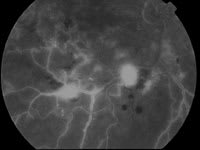

A fluorescein study on March 4, 2002 showed scattered perfusion from microaneurysms O.S. greater than O.D. (see figure 2). The patient was treated with focal grid argon laser, with 27 burns O.D. and 57 O.S.

4. Fluorescein angiography shows severity of retinal edema in the right eye with flame and dot-blot type hemorrhages. |